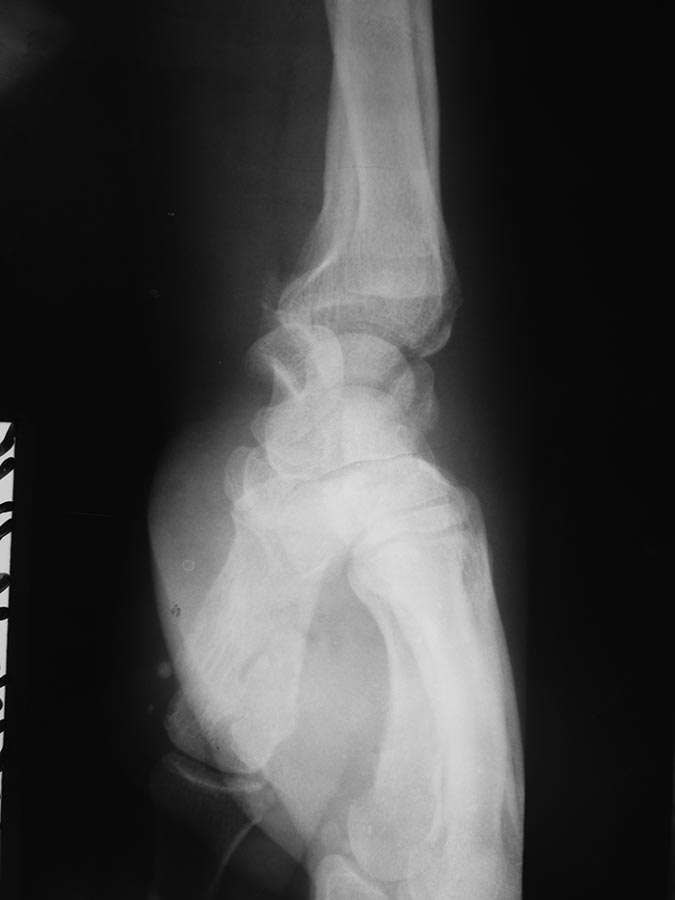

[Ortho] Застарелый вывих полулунной кости

Поступил пациент В, 49 лет. С жалобами: на ограничение движение в правом

лучезапястном суставе, на жжение в пальцах правой кисти в ночное время.

Анамнез: получил травму 25.12.2015 г. лечили амбулаторно перелом лучевой

кости, наложена гипсовая лонгета. После снятие гипса

легча не стало. Амбулаторные снимки прилагаются. Выполнили КТ DS:

признаки вывиха полулунной кости, срастающийся перелом лучевой кости

дистального эпифиза, трехгранной кости. Нужна помощь в тактике лечения.